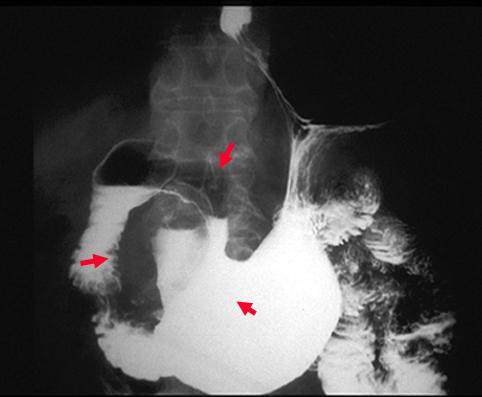

疾患(病理主体)の分類悪性上皮性腫瘍/未分化癌

部位(臓器別)胃(部位)/前庭

検査方法X-P

腫瘍の肉眼分類2型(潰瘍限局型)/

病変の最大径(ミリ)40以上

腫瘍の深達度s(a)